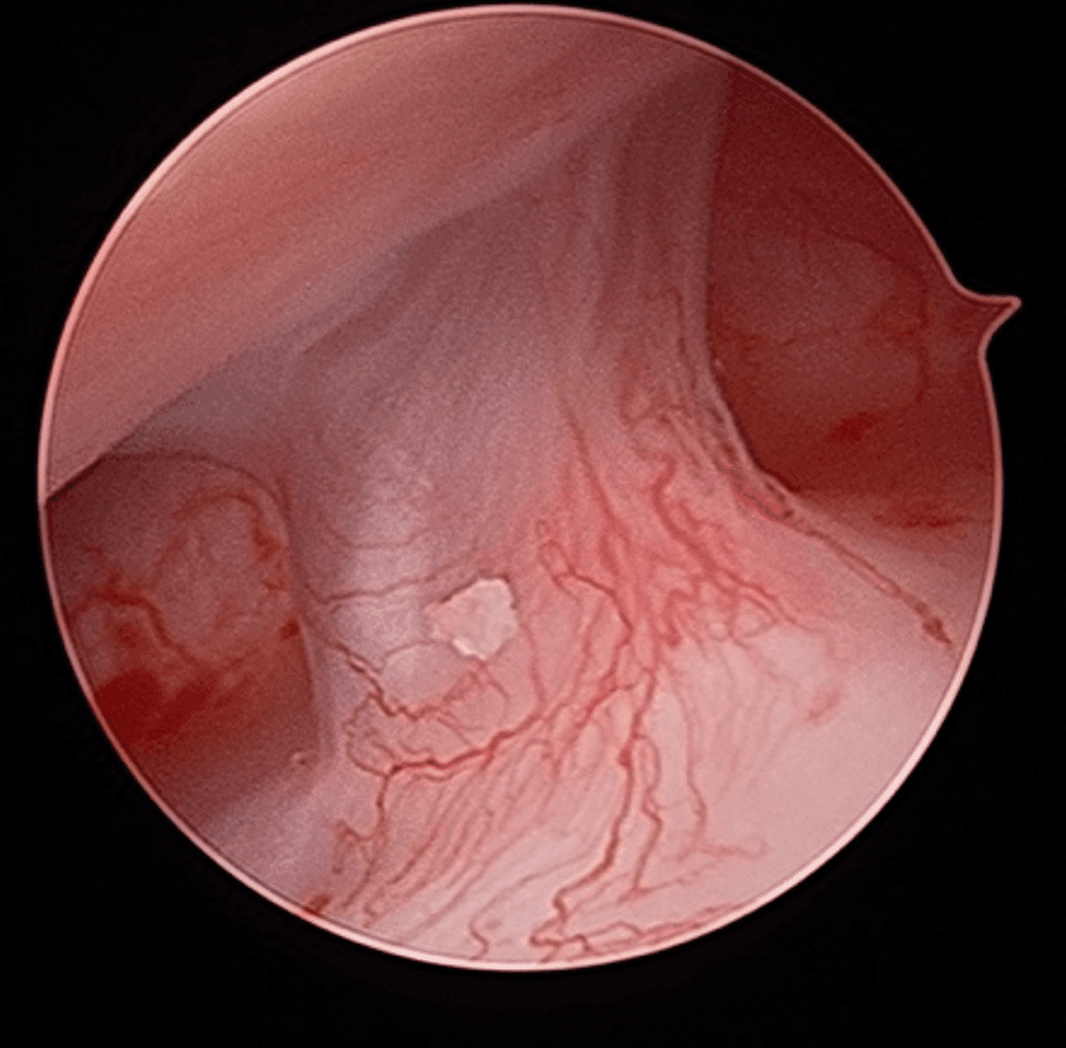

However, some TMDs may require a surgical approach due to their nature or the significant impact they have on function. As a general rule, the surgeon tends to choose the minimally invasive approach that is most appropriate in the circumstances. This may involve a simple joint injection, camera surgery (arthroscopy; an approach that allows access and manipulation of the joint contents without having to open it), or in some cases, open surgery (arthrotomy). Drs. Poirier and Badri have expertise in these fields of practice through their experience and specialization.

Arthroscopic Surgery